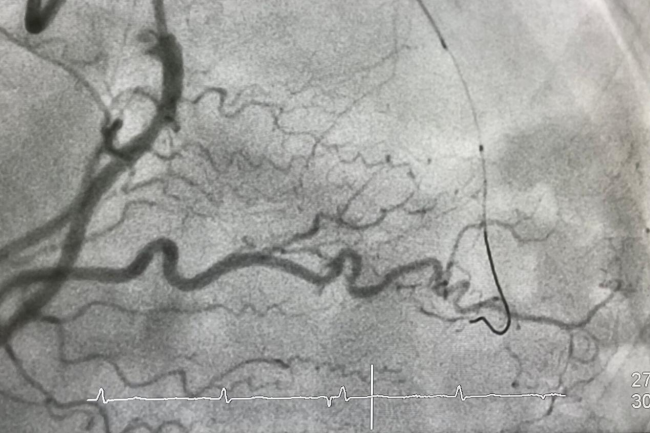

經(jīng)導(dǎo)管輔件用于在患者的心血管系統(tǒng)中安全導(dǎo)航,以到達(dá)特定手術(shù)(如血管成形術(shù)、斑塊切除術(shù)或瓣膜置換術(shù))的目標(biāo)位置。這些裝置負(fù)責(zé)協(xié)助手術(shù)進(jìn)入、在動(dòng)脈路徑中導(dǎo)航,并輸送特定手術(shù)所需的器械和植入物。它們經(jīng)過(guò)特別設(shè)計(jì),具備多種尺寸和配置,以適應(yīng)不同患者間多樣的解剖結(jié)構(gòu)差異,從而在各類心血管介入治療中支持獲得良好的治療效果。

GlobalData 醫(yī)療事業(yè)部咨詢高級(jí)總監(jiān) Charlie Whelan 表示:“要更換一個(gè)主動(dòng)脈瓣,導(dǎo)管需要通過(guò)患者手臂或腹股溝的穿刺口一路蜿蜒進(jìn)入體內(nèi),直達(dá)心臟,而所經(jīng)過(guò)的血管細(xì)得像意大利面一樣。這樣的導(dǎo)管須具備足夠的可扭轉(zhuǎn)性,能夠彎曲和轉(zhuǎn)向,有時(shí)甚至達(dá)到 180 度,同時(shí)不能對(duì)心臟系統(tǒng)或身體的其它部位造成任何損傷。”Charlie補(bǔ)充道:“因此,醫(yī)療器械行業(yè)的關(guān)注點(diǎn),自然集中在能夠讓侵入性操作技術(shù)更加高效的創(chuàng)新上,從而減少手術(shù)中的創(chuàng)傷,并降低患者的風(fēng)險(xiǎn)。”